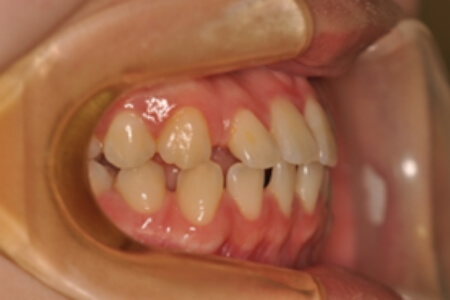

すきっ歯・正中隔離(非抜歯)【0625】

初診時

治療内容の詳細 初診時21歳の女性で、上顎前歯部の隙間(正中離開)を主訴として来院されました。

検査の結果、上下顎前歯部に空隙を伴うアングルⅠ級不正咬合と診断しました。

治療としては、非抜歯の上、マウスピース矯正装置(インビザライン)で配列を行いました。